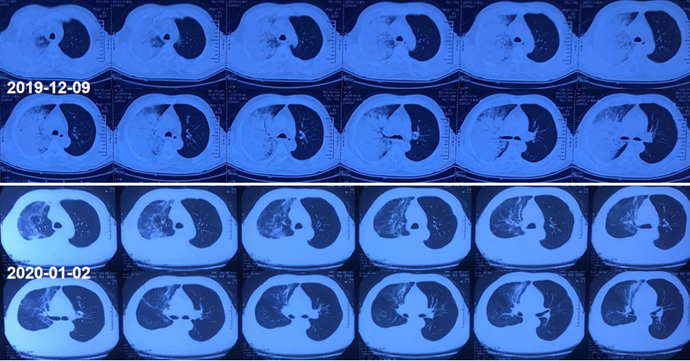

患者,男性,60岁;咳嗽、咳痰、发热1周,加重3天,呼吸困难1天,2019年12月9日入院。最高体温39.5℃,伴头痛、肌肉酸痛、咽痛、打喷嚏、流清涕、言语不利。入院当日胸部CT:右肺上叶实变,右肺下叶背段含气囊肿,右侧胸腔积液(图4)。血气分析:FiO2 53%,pH 7.506,PaCO2 28.5 mmHg,PaO2 54.5 mmHg,PaO2/FiO103 mmHg,K+ 3.0 mmol/L,Na+ 124 mmol/L。

图4  患者胸部CT

入院后患者病情迅速恶化(图5),12月11日行气管插管机械通气。

给予针对性抗感染治疗后,患者氧合指数逐渐升高,吸氧浓度逐渐下调,WBC基本正常,PCT逐渐下降。患者胸部CT较前明显改善(图6)

图6  患者治疗前后胸部CT比较